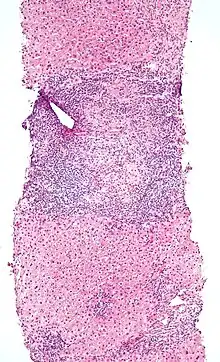

| Micrograph of PBC showing bile duct inflammation and injury, H&E stain | |

Low-magnification micrograph of PBC, H&E stain

On microscopic examination of liver biopsy specimens, PBC is characterized by chronic, nonsuppurative inflammation, which surrounds and destroys interlobular and septal bile ducts. These histopathologic findings in primary biliary cholangitis include:[32]

- Inflammation of the bile ducts, characterized by intraepithelial lymphocytes

- Periductal epithelioid granulomas.

- Proliferation of bile ductules

- Fibrosis (scarring)